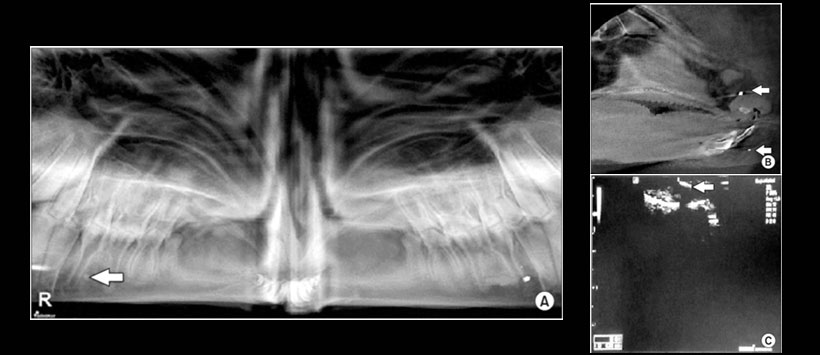

Figura 2: A. Vista de radiografía panorámica de metal de 2 mm (izquierda) y piedra de 2 mm (derecha) en la superficie del hueso. B. Vista sagital computarizada de haz cónico de 2 mm de metal en el espacio lleno de aire (flecha superior) y fragmento de diente de 1 mm en tejido blando (flecha inferior). C. Vista de ultrasonografía de madera de 2 mm en tejido blando (flecha).

Obteniendo como resultado que la  CBCT fue más precisa en la detección de FB que la radiografía panorámica y la US.  Siendo el metal la FB más visible en todas las muestras. La ultrasonografía fue la técnica más precisa para detectar materiales de madera, y la CBCT fue la mejor modalidad para detectar todos los demás materiales, independientemente del tamaño o la ubicación. La precisión de detección del ultrasonido  fue mayor en tejidos blandos, mientras que tanto la CBCT como la radiografía panorámica tuvieron una precisión mínima en la detección de FB en tejidos blandos.